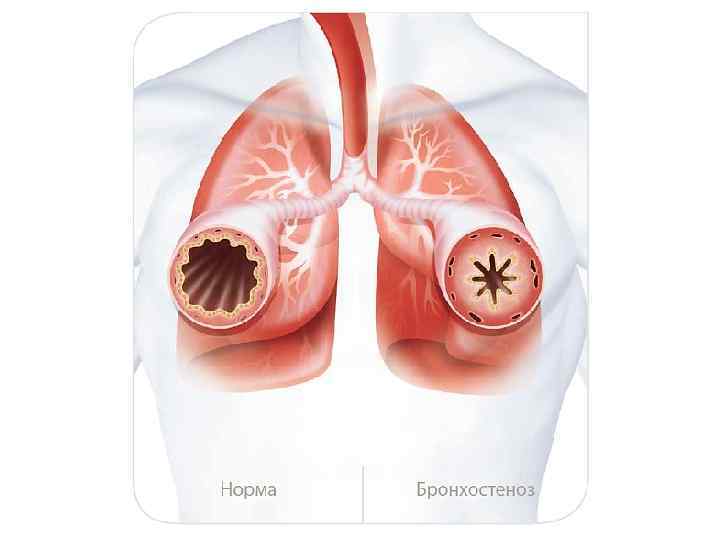

Факторы риска Недостаточное увлажнение дыхательной смеси Высушивание трахеи и бронхов

Факторы риска Недостаточное увлажнение дыхательной смеси Высушивание трахеи и бронхов

Факторы риска Недостаточное увлажнение дыхательной смеси ! Слизистая оболочка трахеи и бронхов обязательно должна быть укрыта секретом

Факторы риска Недостаточное увлажнение дыхательной смеси ! Слизистая оболочка трахеи и бронхов обязательно должна быть укрыта секретом

Факторы риска Недостаточное увлажнение дыхательной смеси • естественное удаление бактерий • состояние эпителия трахеи и бронхов

Факторы риска Недостаточное увлажнение дыхательной смеси • естественное удаление бактерий • состояние эпителия трахеи и бронхов

Факторы риска Недостаточное увлажнение дыхательной смеси Высушивание трахеи и бронхов

Факторы риска Недостаточное увлажнение дыхательной смеси Высушивание трахеи и бронхов

Плохое увлажнение • Вязкая слизь - потеря ресничек • Высушивание слизистой смерть клеток • Высушивание слизи в бронхиолах-ателектазы • Затраты энергии на согревание воздуха • Затраты воды на увлажнение

Плохое увлажнение • Вязкая слизь - потеря ресничек • Высушивание слизистой смерть клеток • Высушивание слизи в бронхиолах-ателектазы • Затраты энергии на согревание воздуха • Затраты воды на увлажнение